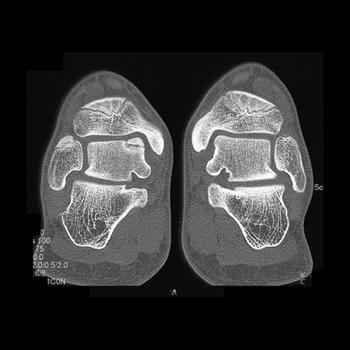

If suspected, imaging begins with conventional radiographs. Three views of the foot are necessary, as the oblique view is best for detecting calcaneonavicular and talonavicular coalitions. However, talocalcaneal coalitions are not as reliably diagnosed with conventional radiographs, and often require CT or MRI to detect. CT is helpful in any type of coalition to elucidate whether the union is osseous, fibrous or cartilaginous, to detect secondary OA, and for preoperative determination of the extent of joint involvement and the appropriate type of surgical treatment. Postoperatively, CT can confirm whether a coalition has recurred or detect secondary osteoarthritis.

Talocalcaneal coalitions may not be apparent on oblique conventional radiographs, and MDCT is an excellent modality with which to evaluate the foot if this suspected. The narrow collimation of MDCT and the high quality 3D reconstructions are helpful in evaluating these coalitions with high resolution datasets, which can be viewed in any orientation. This is particularly helpful for detecting talocalcaneal coalitions, which are best visualized in the coronal plane. With MDCT, the high resolution multiplanar reconstructions preclude the requirement for direct coronal acquisitions. These unions usually join the middle facet of the talus to the sustentaculum tali of the calcaneus. An osseous bridge will be apparent if the union is bony. In cartilaginous coalitions, the middle facet joint is markedly narrowed with cortical irregularity. Fibrous coalitions demonstrate slight narrowing of the middle facet joint, and were the most difficult to detect in one series with surgical correlation.

Specific imaging findings have been shown to correlate with the outcome of a talocalcaneal coalition and can be used to determine whether the treatment should be resection or immobilization. CT can be used to measure the coalition area and detect osteoarthritis. Resection is indicated if the area is less than 50% of the surface area of the talocalcaneal joint and if secondary degenerative osteoarthritis is not detected in the talonavicular joint.